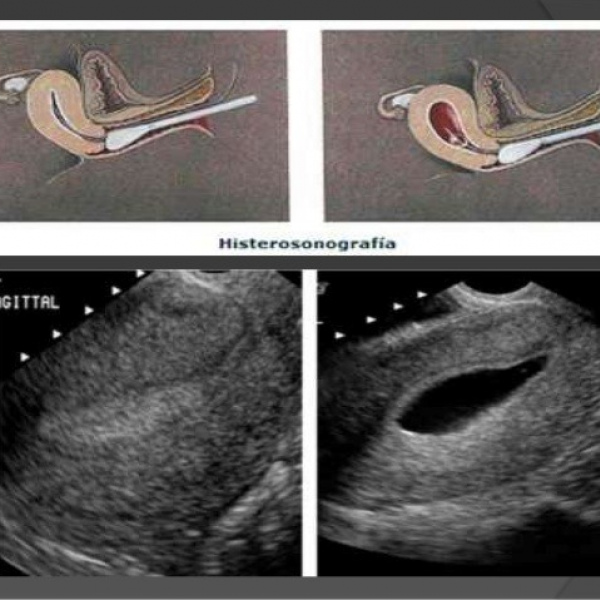

Ecografia pelvica ginecologica:histerosonografia o histerosalpingosonografia. 881410 Idime